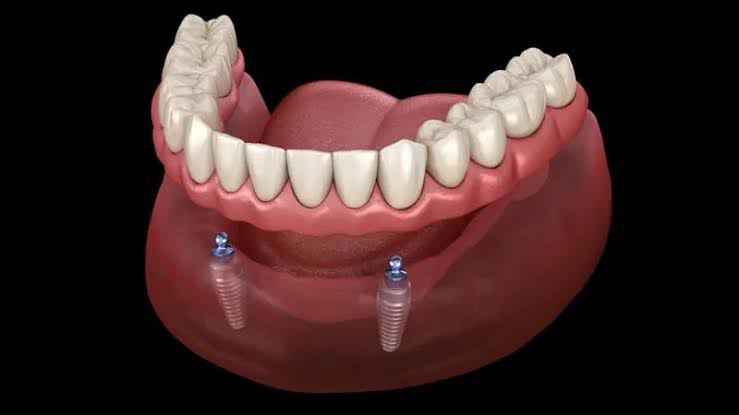

Prótese removível que se fixa em implantes, oferecendo muito mais estabilidade e conforto do que dentaduras tradicionais.